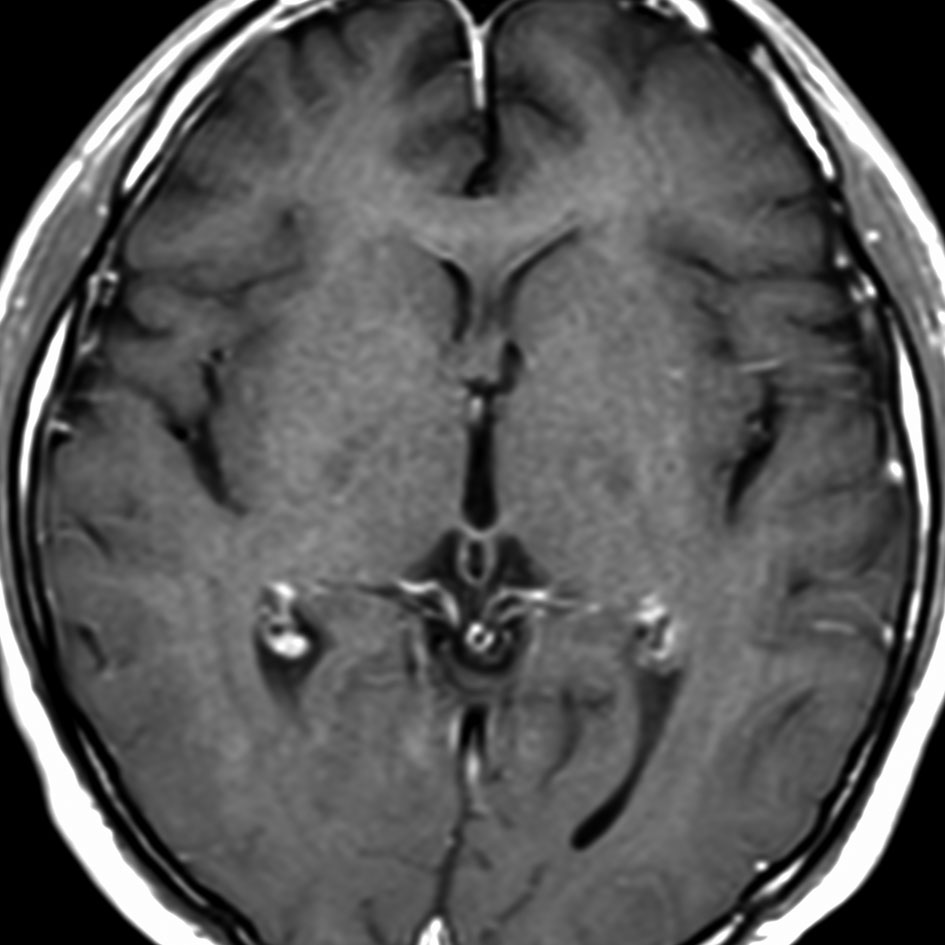

ガドリニウム増強では,前頭葉腫瘍というより,側脳室壁にベトベトくっついているような腫瘍です。germinoma特有のsubependymal infiltration像を示します。

発見時に無症状で尿崩症もなにもなく,下垂体にも松果体にも腫瘍はありませんでした。

21歳男性で交通事故で偶然発見された両側前頭葉腫瘍です。